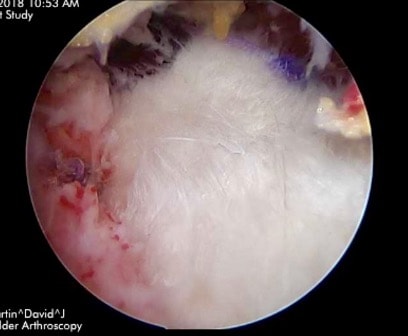

LARGE ROTATOR CUFF TEAR